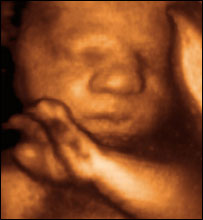

20周的婴儿胚胎像

女友怀孕20多个星期时作过三维B超,并且录制了DVD。看光盘的时候开玩笑,孩子的小蒜头鼻子长得像她!爸爸则自豪地大喊,“他的大奔儿头正好像我!”

技术的进步,使人们能够越来越早地和腹中的胎儿会面,也使人们对堕胎的态度发生转变。